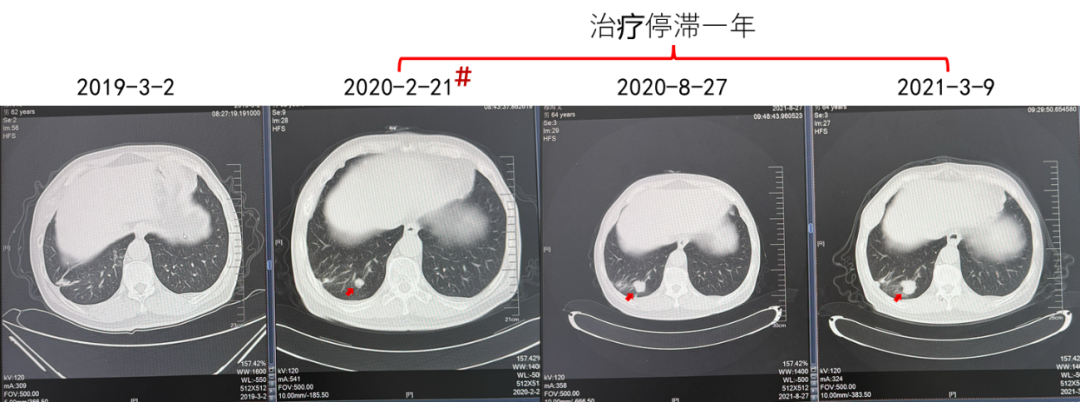

(治疗停滞1年,患者对侧肾上腺肿瘤发生进展)

第三阶段:靶免联合+射波刀

2021.03阿昔替尼5mg BD+帕博利珠单抗200 mg+射波刀

疗效:肺部病灶疾病稳定(4年)。对侧肾上腺病灶部分缓解(4年)。

由于患者中间治疗停滞一年,可能导致了肿瘤的进一步发展,因而需要针对对侧肾上腺肿瘤进行治疗。对于一线TKI单药治疗后进展的患者,目前多推荐更改为以ICI为基础的靶免联合治疗方案。而对于靶免联合治疗后进展的患者,需要充分考虑患者危险因素与危险分层、药物疗效与耐受性,综合选择治疗方案。